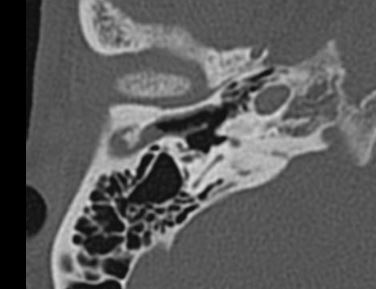

先天性外耳道狹窄,鼓膜穿孔,能做微創(chuàng)手術(shù)嗎

最近來自廣東潮州的吳先生找到耳鼻喉鄭立崗醫(yī)生要求治療自己的中耳炎鼓膜穿孔。但是陳先生的情況非常特殊,雙側(cè)外耳道先天性狹窄,手術(shù)操作的空間過于狹窄,按正常的手術(shù)步驟是做不了的。入院完善檢查后,耳鼻喉鄭立崗醫(yī)生考慮耳內(nèi)鏡中耳炎微創(chuàng)手術(shù)可以做但是要先在耳內(nèi)鏡下擴(kuò)大外耳道后再修補(bǔ)鼓膜,要不然手術(shù)無法做。制定好方案后就開始了手術(shù),插管全麻后先在耳內(nèi)鏡下用電鉆磨除多余的骨質(zhì),擴(kuò)大外耳道,然后翻起皮瓣,取耳屏軟骨修補(bǔ)鼓膜,整個(gè)的手術(shù)用時(shí)約90分鐘,非常的難做。術(shù)后查房患者無明顯的不適,無面癱等并發(fā)癥。對(duì)于外耳道狹窄的中耳炎鼓膜穿孔的患者,耳內(nèi)鏡下擴(kuò)大外耳道是修補(bǔ)鼓膜的必要步驟。對(duì)于中耳炎微創(chuàng)手術(shù),如果您還有問題,歡迎留言和耳鼻喉鄭立崗醫(yī)生進(jìn)一步交流。